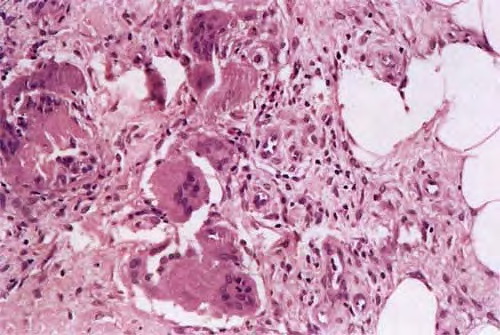

In the early lesions of acute erythema nodosum, there is edema of the septa with a Iymphohistiocytic infiltrate, having a slight admixture of neutrophils and eosinophils . Focal fibrin deposition and extravasation of erythrocytes occur frequently  and can be revealed by spectral microscopy . Often, the inflammation is most intense at the periphery of the edematous septa and extends

into the periphery of the fat lobules between the individual fat cells in a lacelike fashion. Necrosis of the fat is not prominent. Rarely, clusters of neutrophils are present or the infiltrate is predominantly neutrophilic . Clusters of macrophages around small blood vessels, or a slitlike space, occur in early lesions and are known as Miescher's radial nodules . Some authors have failed to find central vessels  and have considered Miescher's nodules to be characteristic of erythema nodosum, stating that they can be found in all stages of erythema nodosum . The degree of vascular involvement is variable . Usually, there is edema of the walls of veins with separation of the muscular layers . Infiltration by lymphocytes is common, but neutrophils and eosinophils can be present as well. Necrosis of the vessel walls is very rare but has been observed in a few patients with lesions clinically indistinguishable from erythema nodosum . For example, focal vasculitis has been found in a few patients with acute erythema nodosum secondary to infections  and in a few cases of recurrent

Later lesions of acute erythema nodosum show widening of the septa, often with fibrosis and with inflammation at the edges of the septa and involving the periphery of the fat lobules . Neutrophils usually are absent, and the vascular changes are less prominent than in early lesions. There are more macrophages in the infiltrate. Macrophages at the edges of the fat lobules show phagocytosis of lipid from damaged adipocytes, and the small droplets of lipid in their cytoplasm give them a "foam cell" appearance. Granulomas formed by macrophages, without lipid deposition, are more frequent

when late lesions are compared with early ones . The granulomas often are loosely formed with macrophages predominating in a focus with multinucleated giant cells. Occasionally, well-formed, discrete sarcoidal granulomas occur in small numbers in the septa. The multinucleated cells usually have an irregular distribution of the nuclei in the cytoplasm. The oldest lesions have septal widening and fibrosis with a decrease in all of the inflammatory cells.